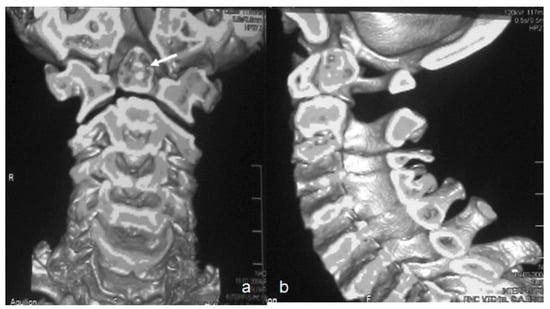

Reformatted CT scan of the craniocervcial and the cervical vertebrae of the proband showed odontoid hypoplasia secondary to neurocentral synchodrosis and defective formation of the cervical vertebrae in connection with synchondrosis. The latter is the development of union between two bones by the formation of either hyaline cartilage of fibrocartilage. A synchondrosis is usually temporary and exists during the growing phase until the intervening cartilage becomes progressively thinner during skeletal maturation and is ultimately obliterated and converted into bone before adult life. In other words, a synchondrosis is a cartilaginous joint. It allows only slight movement between bones compared to the synovial joint, which has a much greater range of movement. The process of ossification within the centrum of the vertebral body is similar to that of tertiary ossification. Longitudinal growth mostly occurs at the chondro-epiphyseal portions of the end-plates. In this patient, it was obvious that synchondrosis was a permanent rather than a temporary process. Reformatted Coronal CT scan of the cervical spine showed butterfly vertebrae (defective formation), note the detached cephalic part of the odontoid process (arrowhead) in connection with extensive cervical spine synchondrosis causing the mal-development of butterfly vertebrae (Figure 1a). Reconstruction CT scan of the cervical spine showed atlanto-axial dislocation (arrows). Both parents experienced low backpain since their late adolescence (spondylolisthesis was the diagnosis). AP radiograph of the lumbar vertebrae at the age of 32-year-old mother showed osteoarthritis of the facet joints of L5 (arrow) associated with diminution of the heights of L4/5. Note the increased level of calcification that signifies facet arthritis. Surprisingly, the AP pelvis radiograph of the mother at age of 32 years showed incidental diagnosis of ossification of the abdominal aorta. The mother is asymptomatic, but such finding is of utmost importance. Ossification of the abdominal aorta signifies a state of subclinical atherosclerosis with subsequent vascular hazards-red arrowhead (Figure 2a). Sagittal spine MRI of the 38-year-old father showed dysplastic spondylolisthesis of L4/5 (arrow) that might leads to spinal stenosis (Figure 2b). Phenotype/genotype of the family with spondylo-meg-epiphyseal-dysplasia appears in Table 1.

Figure 1. (a). Reformatted Coronal CT scan of the cervical spine showed butterfly vertebrae (defective formation), note the detached cephalic part of the odontoid process (arrowhead) in connection with extensive cervical spine synchondrosis causing the mal-development of butterfly vertebrae. (b) Reconstruction CT scan of the cervical spine showed atlanto-axial dislocation (arrows).